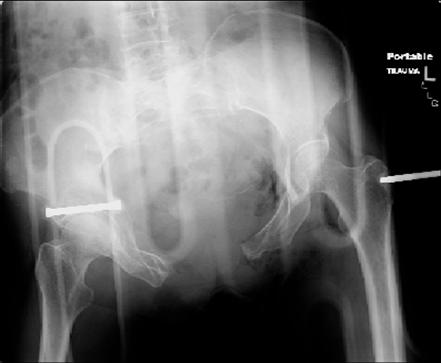

injuries are limited to the pelvis. left rami open and visible in a 10cm vertical laceration just lateral to left labia majora. wound is grossly clean. no vaginal and no urinary issues. CT scan shows widening of both SI joints anteriorly but I think this is vertically stable pattern.

pt treated that night with I/D and supra-acetabular frame to close the ring. consideration was given for SI screws bilateraly, but given time of night and other factors decision made not to proceed.

so the question is what next operatively if anything? concerns are infection, nonunion anteriorly and possible incompetence of the pelvic floor which may lead to prolapse issues. right rami are comminuted and plating may entail ilioinguinal approach to extend plate laterally to right iliac wing. retrograde screw up right rami is an option but I am not convinced it will add much. adding SI screws very doable, but major concern is restoring anterior ring. so far wound is clean and closed over a drain, and I have no plans to open it back up and wash again.

any thoughts? would anyone plate the pubic symphysis to close the gap and leave the more lateral rami fractures alone? the most recent pelvic case on this website involved pts with suprapubic catheters and antibiotic options including resorbable beads. I wonder how many people would plate and place antibiotic beads. thanks.